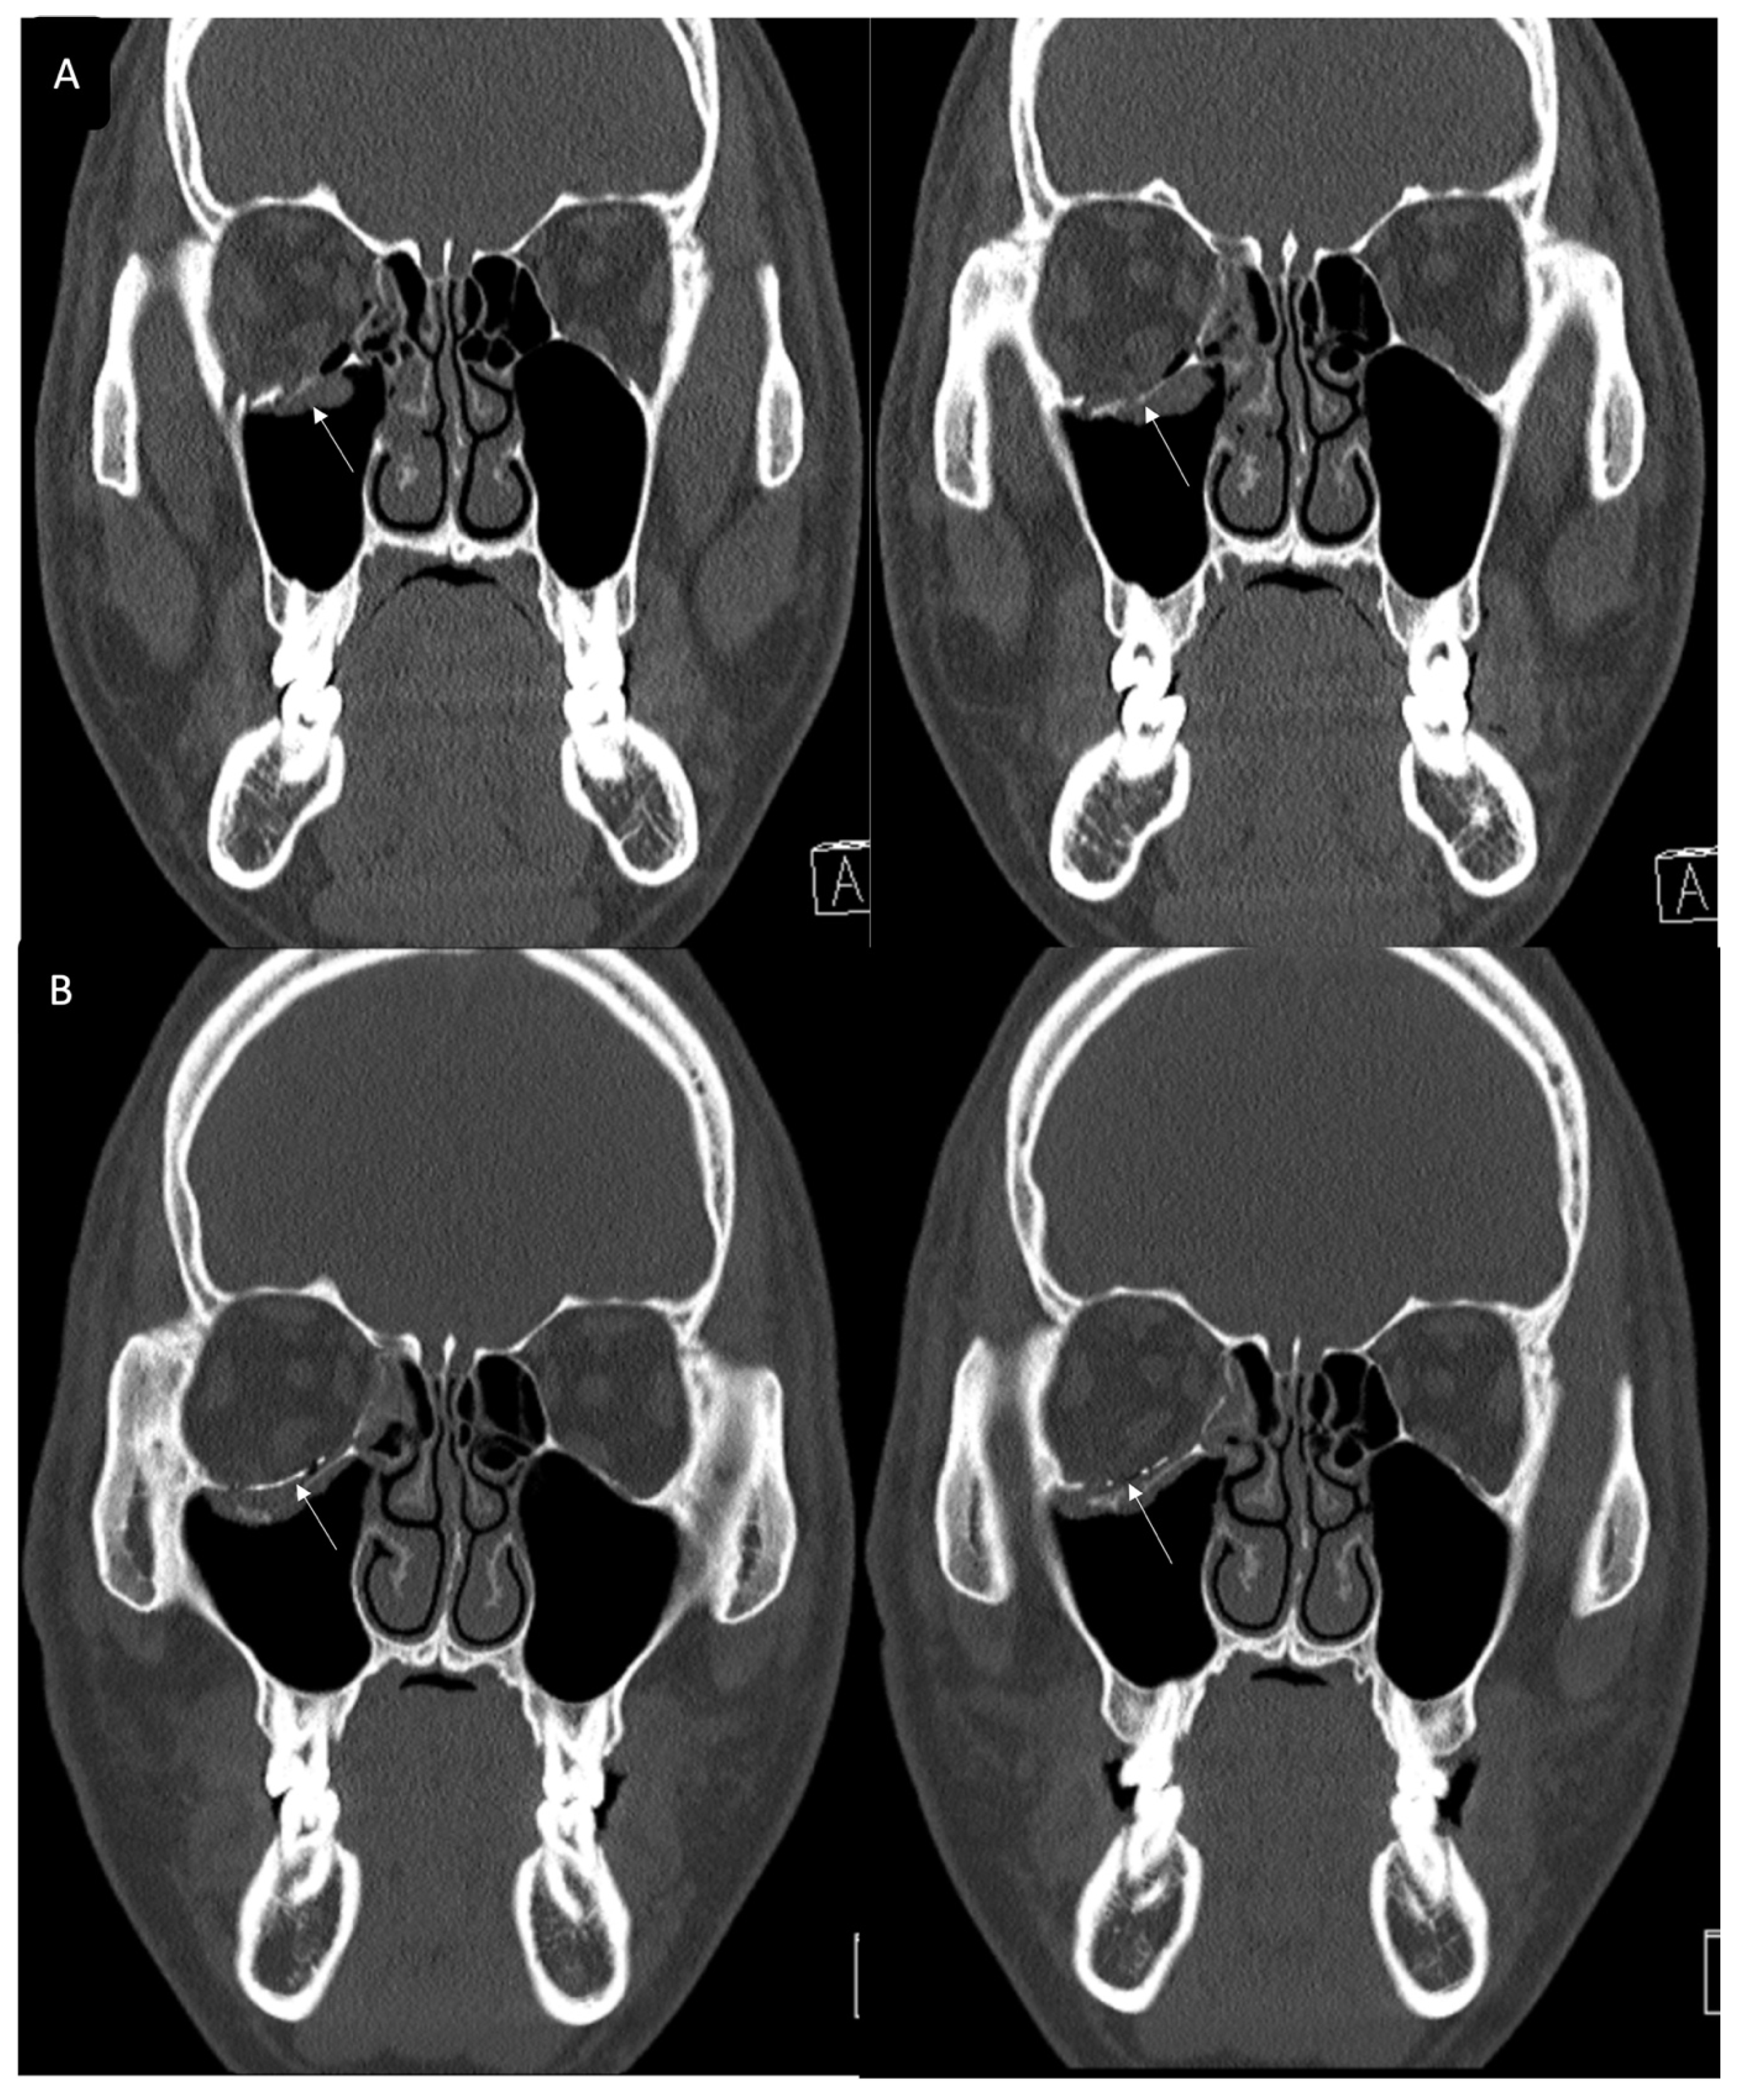

Figure 3. Case 2. Preoperative facial CT scan (coronal view) of the 48-year-old female patient with left inferomedial orbital wall fracture. The titanium-reinforced porous polyethylene (TR-PPE) plate was placed on the inferomedial orbital wall using a single screw at the inferior orbital rim. (White arrow).

Figure 4. Case 2. Follow up facial CT finding (coronal view) of the same patient. The titanium-reinforced porous polyethylene (TR-PPE) plate was placed on the inferomedial orbital wall using a single screw at the inferior orbital rim. (White arrow).

3.2. Case 2

A 48-year-old female patient came to our clinic with left eyeball swelling and ecchymosis caused by a car accident. The patient complained of pain and discomfort with eyeball movement (Figure 3). We surgically approached the medial orbital wall fracture seven days after the accident. After the subciliary incision, the fracture was exposed. The titanium-reinforced porous polyethylene (TR-PPE) plate was placed on the fracture site using a single screw at the inferior orbital rim (Figure 4). The patient was discharged on postoperative day 2 with significantly improved pain and discomfort.